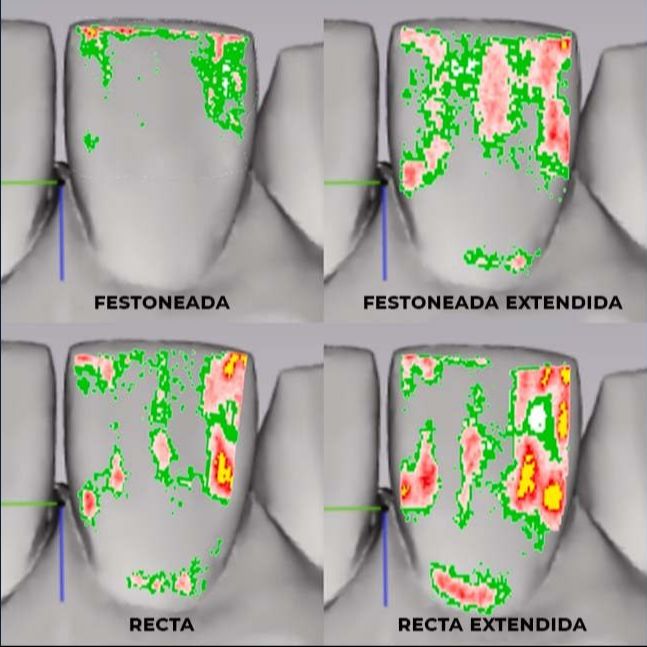

¿Influye el Diseño de recorte de los Alineadores en el tratamiento?

Este estudio reciente ha investigado cómo la distribución de estrés y las fuerzas transmitidas de los alineadores a la superficie dental se ven afectadas por la geometría y extensión de la línea de recorte. Los resultados de este estudio revelaron que esto puede tener un impacto significativo en los resultados clínicos del tratamiento.